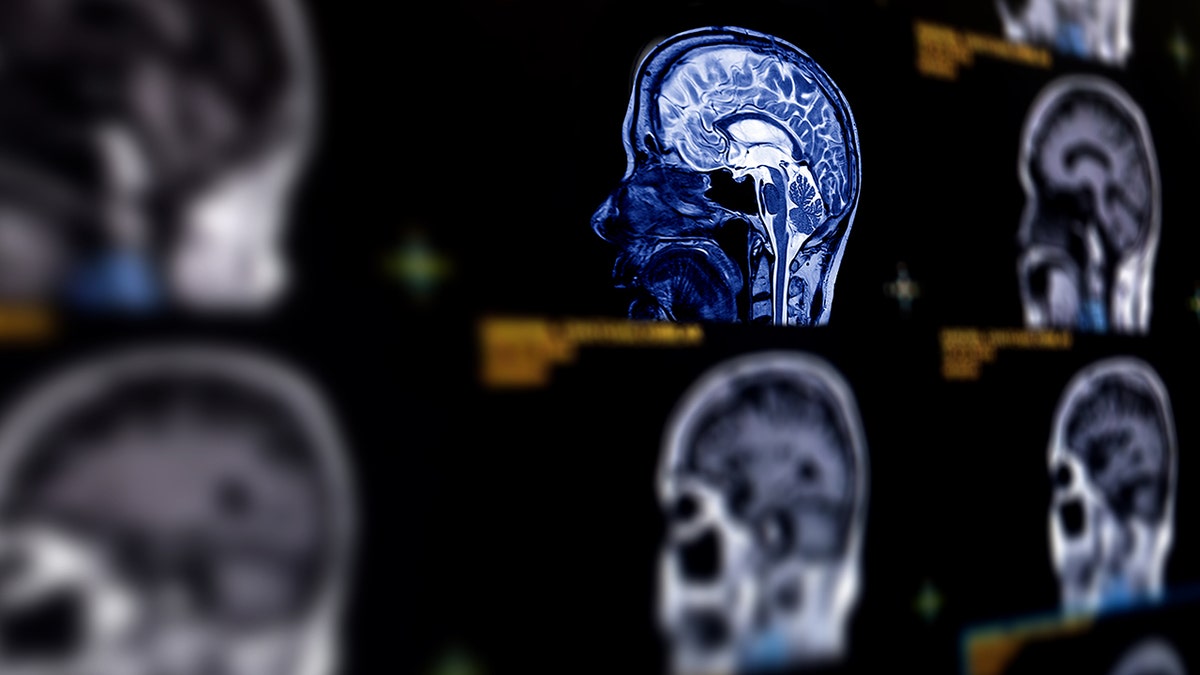

A severe headache may occur if a brain aneurysm becomes problematic. (iStock)

Stroke is the leading cause of disability in the U.S., which “disables way more people than it outright kills,” a doctor said. (iStock)